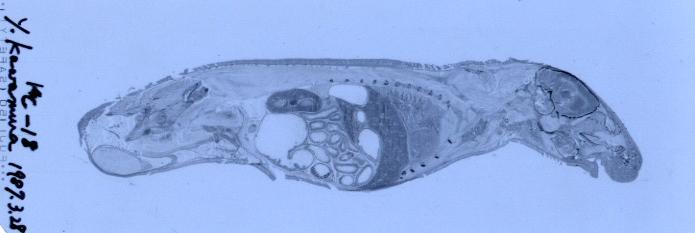

放射線で撮影した写真(X線フィルム)

1.インゲン豆でのSr 2.インゲン豆でのC14 3.マウスでのC14

植物の場合,SrなどはCaのように骨格部(茎)に集まりやすく,Cは光合成により葉に集まりやすい。